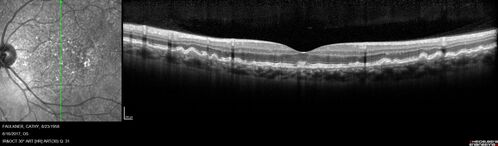

Soft Drusen

63 year old female with 20/16 vision both eyes